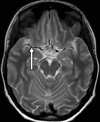

4

Q

A

falx cerebri